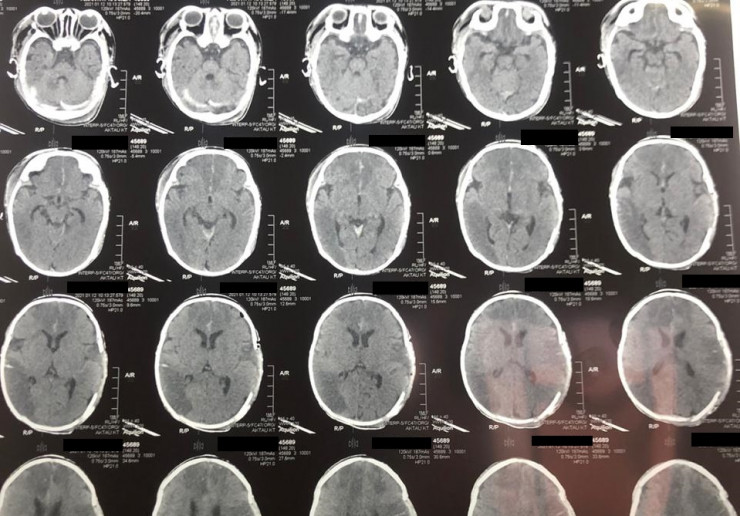

У младенца случился инсульт в Мангистауской области. Ребенка с диагнозом "острое нарушение мозгового кровообращения" (инсульт новорожденных) доставили в Мангистаускую областную многопрофильную детскую больницу 9 января, передает Tengrinews.kz со ссылкой на "Лада".

Как сообщили в больнице, у двухмесячного младенца из-за инсульта зафиксировали отек головного мозга, дислокационный синдром и кому I-II степени. Благодаря усилиям врачей 10 января состояние ребенка удалось стабилизировать. В экстренном порядке ему провели операцию по трепанации черепа, которая продлилась два часа.

Фото: lada.kz/Ербол Кенжевалов

"Такие случаи редко заканчиваются положительным результатом, но нам удалось спасти ребенка. В настоящий момент пациента перевели в отделение травматологии, он находится в среднетяжелом состоянии", - сообщил детский нейрохирург Ербол Кенжевалов.